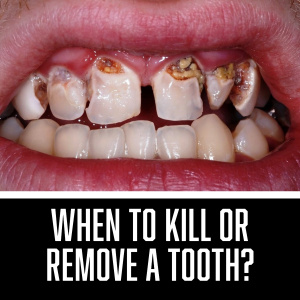

When to Kill or Remove a Tooth?Gordon J. Christensen, DDS, MSD, PhD & Valinda Johnston, BS, CDA Many different philosophies exist on when to do endodontics or remove a tooth. Which ones are the best and most conservative? Shou...... |